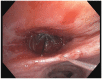

Bronchopleural fistula (BPF) is associated with high morbidity if left untreated. Although rare, the frequency of BPF in severe acute respiratory syndrome coronavirus 2 (SARS-CoV-2) is becoming recognized in medical literature. We present a case of a 64-year-old male with BPF with persistent air leak due to SARS-CoV-2 pneumonia treated with Spiration Valve System endobronchial valve (EBV). An EBV was placed in the right middle lobe with successful cessation of air leak. In conclusion, the use of EBVs for BPF with persistent air leaks in SARS-CoV-2 patients who are poor surgical candidates is effective and safe.